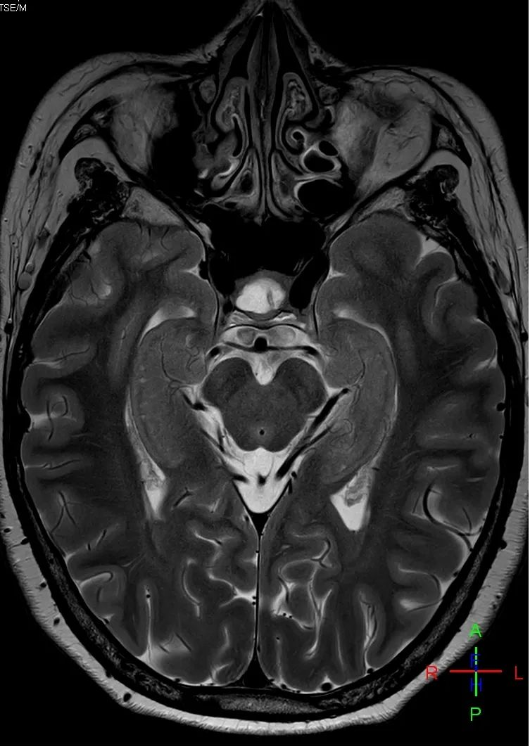

什么是3.0T MRI?

选择3.0T MRI的N个理由

没有图像就没有影像医学,而图像的可靠优质获取是影像医学的基础和前提。3.0T磁共振机的临床使用,不仅能够为患者带来更为精准、便捷、舒适、安心、全面的磁共振检查,同时也将进一步促进我院医疗、教学和科研水平的提高。今后,放射科将更好地利用新设备新技术,为临床诊疗工作做好保障!